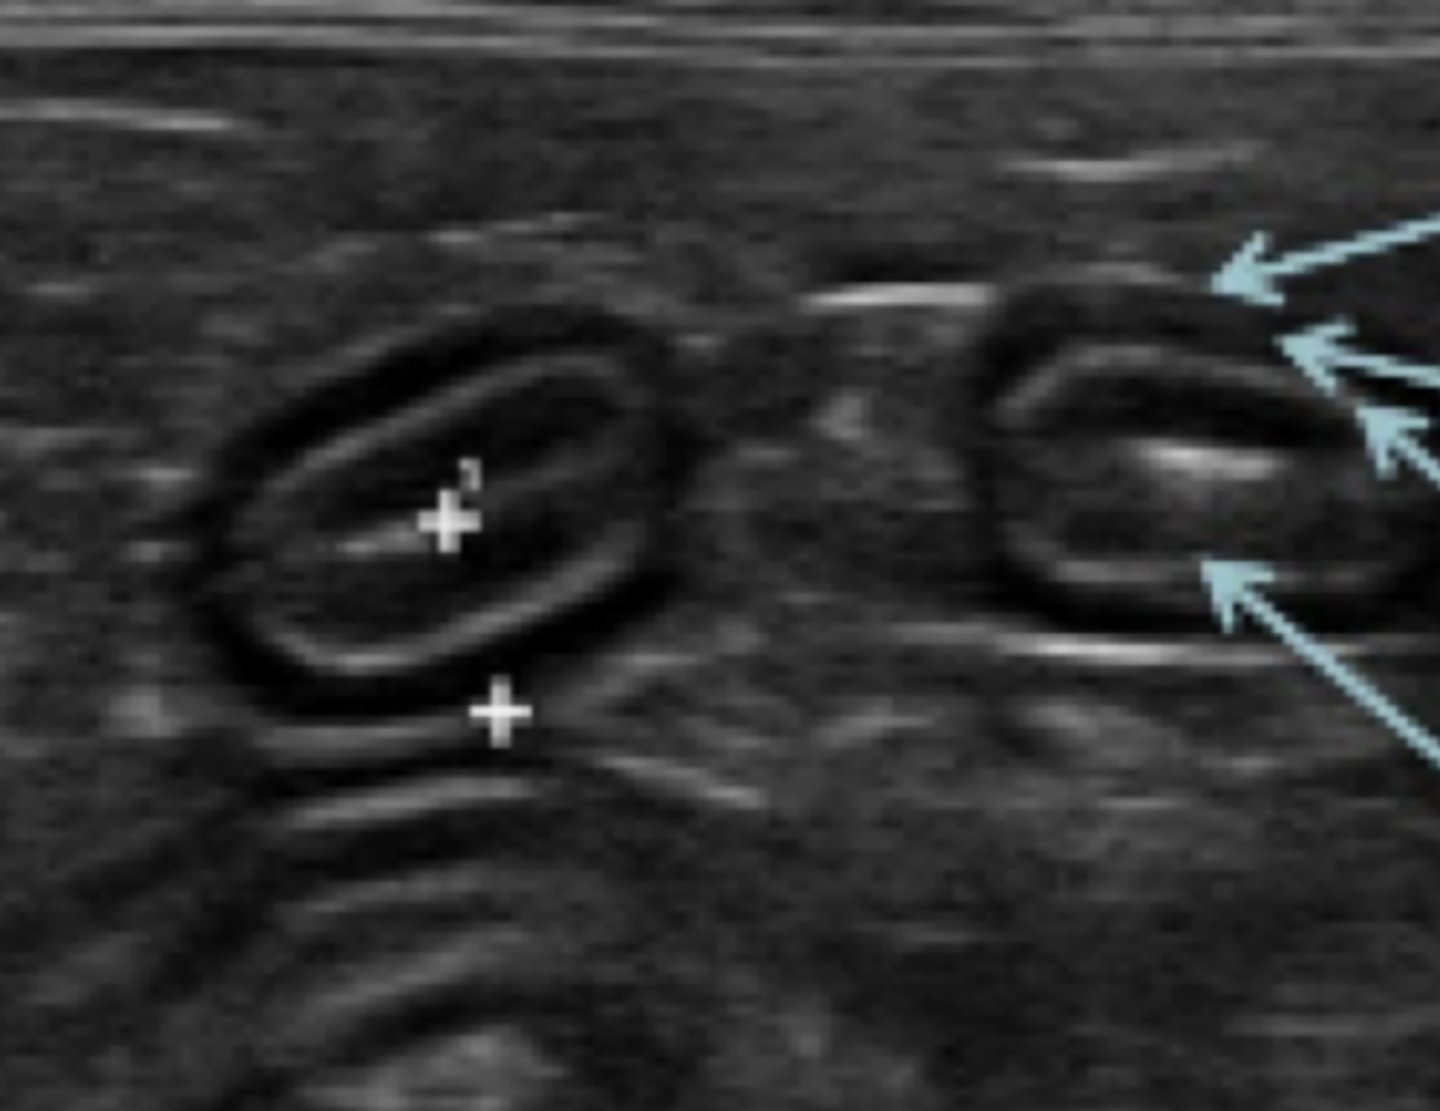

intestino

(corte transversal)

¿qué parte del cuerpo?

(corte longitudinal)

intususcepción

patología: